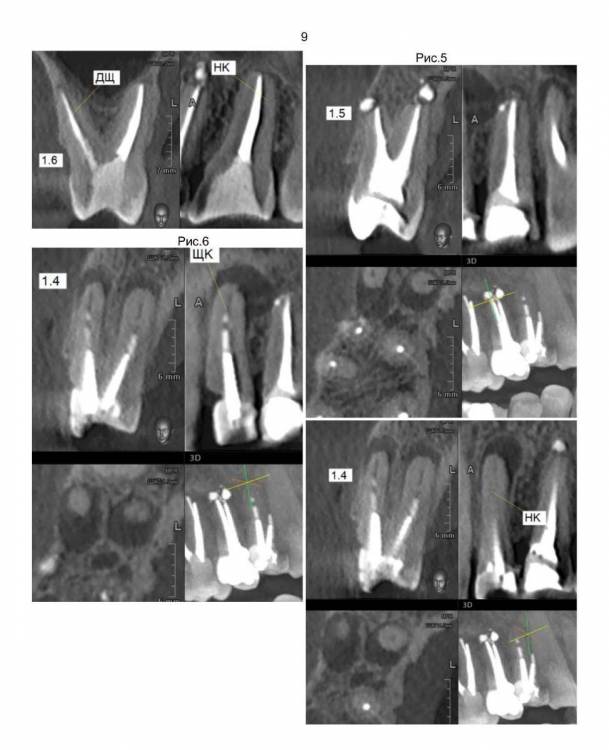

Врач стоматолог написал планы лечения. Больше всего меня смущает удаление трех верхних зубов 1.4, 1.5, 1.6 т.к. на концах корней у этих зубов развиваются опухоли, и установка на их место имплантов сразу после удаления. Правильно ли это? Просто до этого слышал, что перед установкой импланта требуется около трех месяц на заживление. Стоматолог говорит, что надо сразу установить импланты, что бы избежать деформацию десны. Потом через примерно три месяца на эти три импланта будут ставиться коронки.